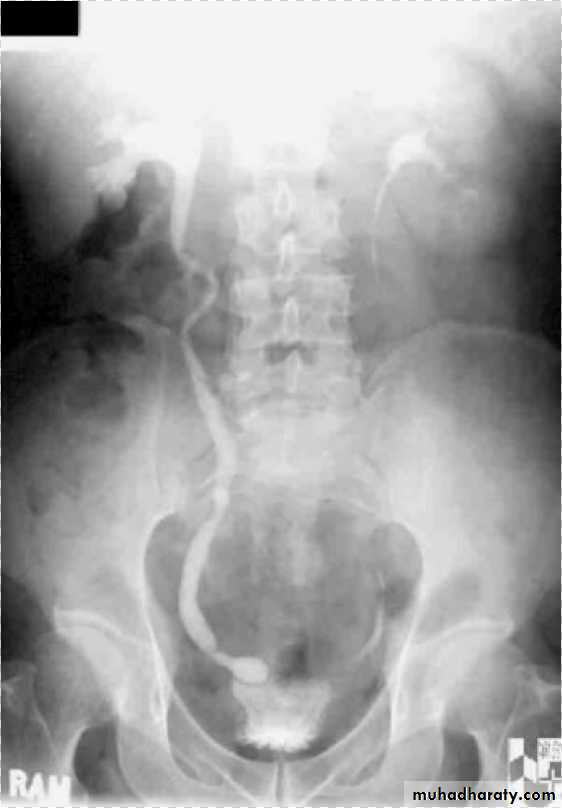

Infantile hydronephrosis ( PUJ OBSTRUCTION ):

IVU shows :

Marked dilatation of pelvis and may be extra-renal.

Calyceal dilatation is late and in advanced cases form foot shape PCS

The ureter is not seen and when it is seen looksnormal .

Delayed film with I.V. diuretic produce gross dilatation .